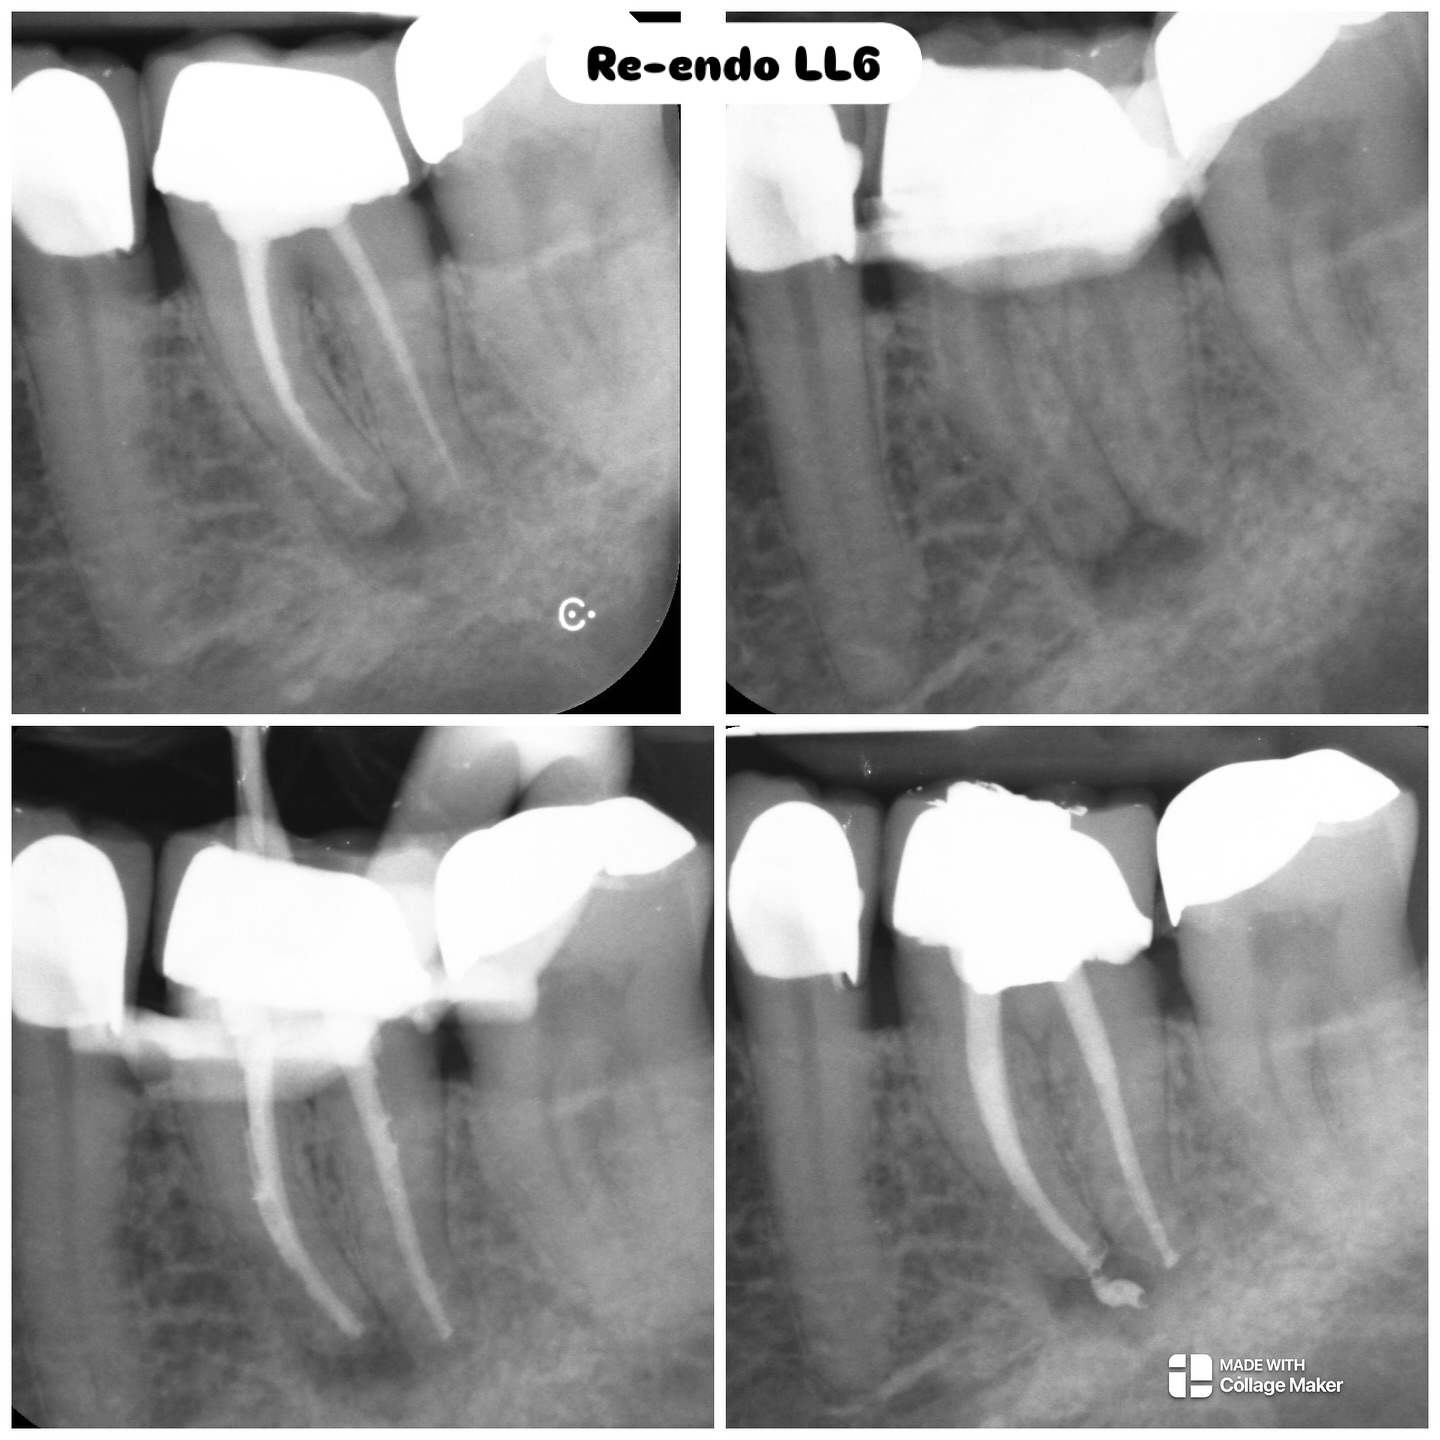

Operative microscopy